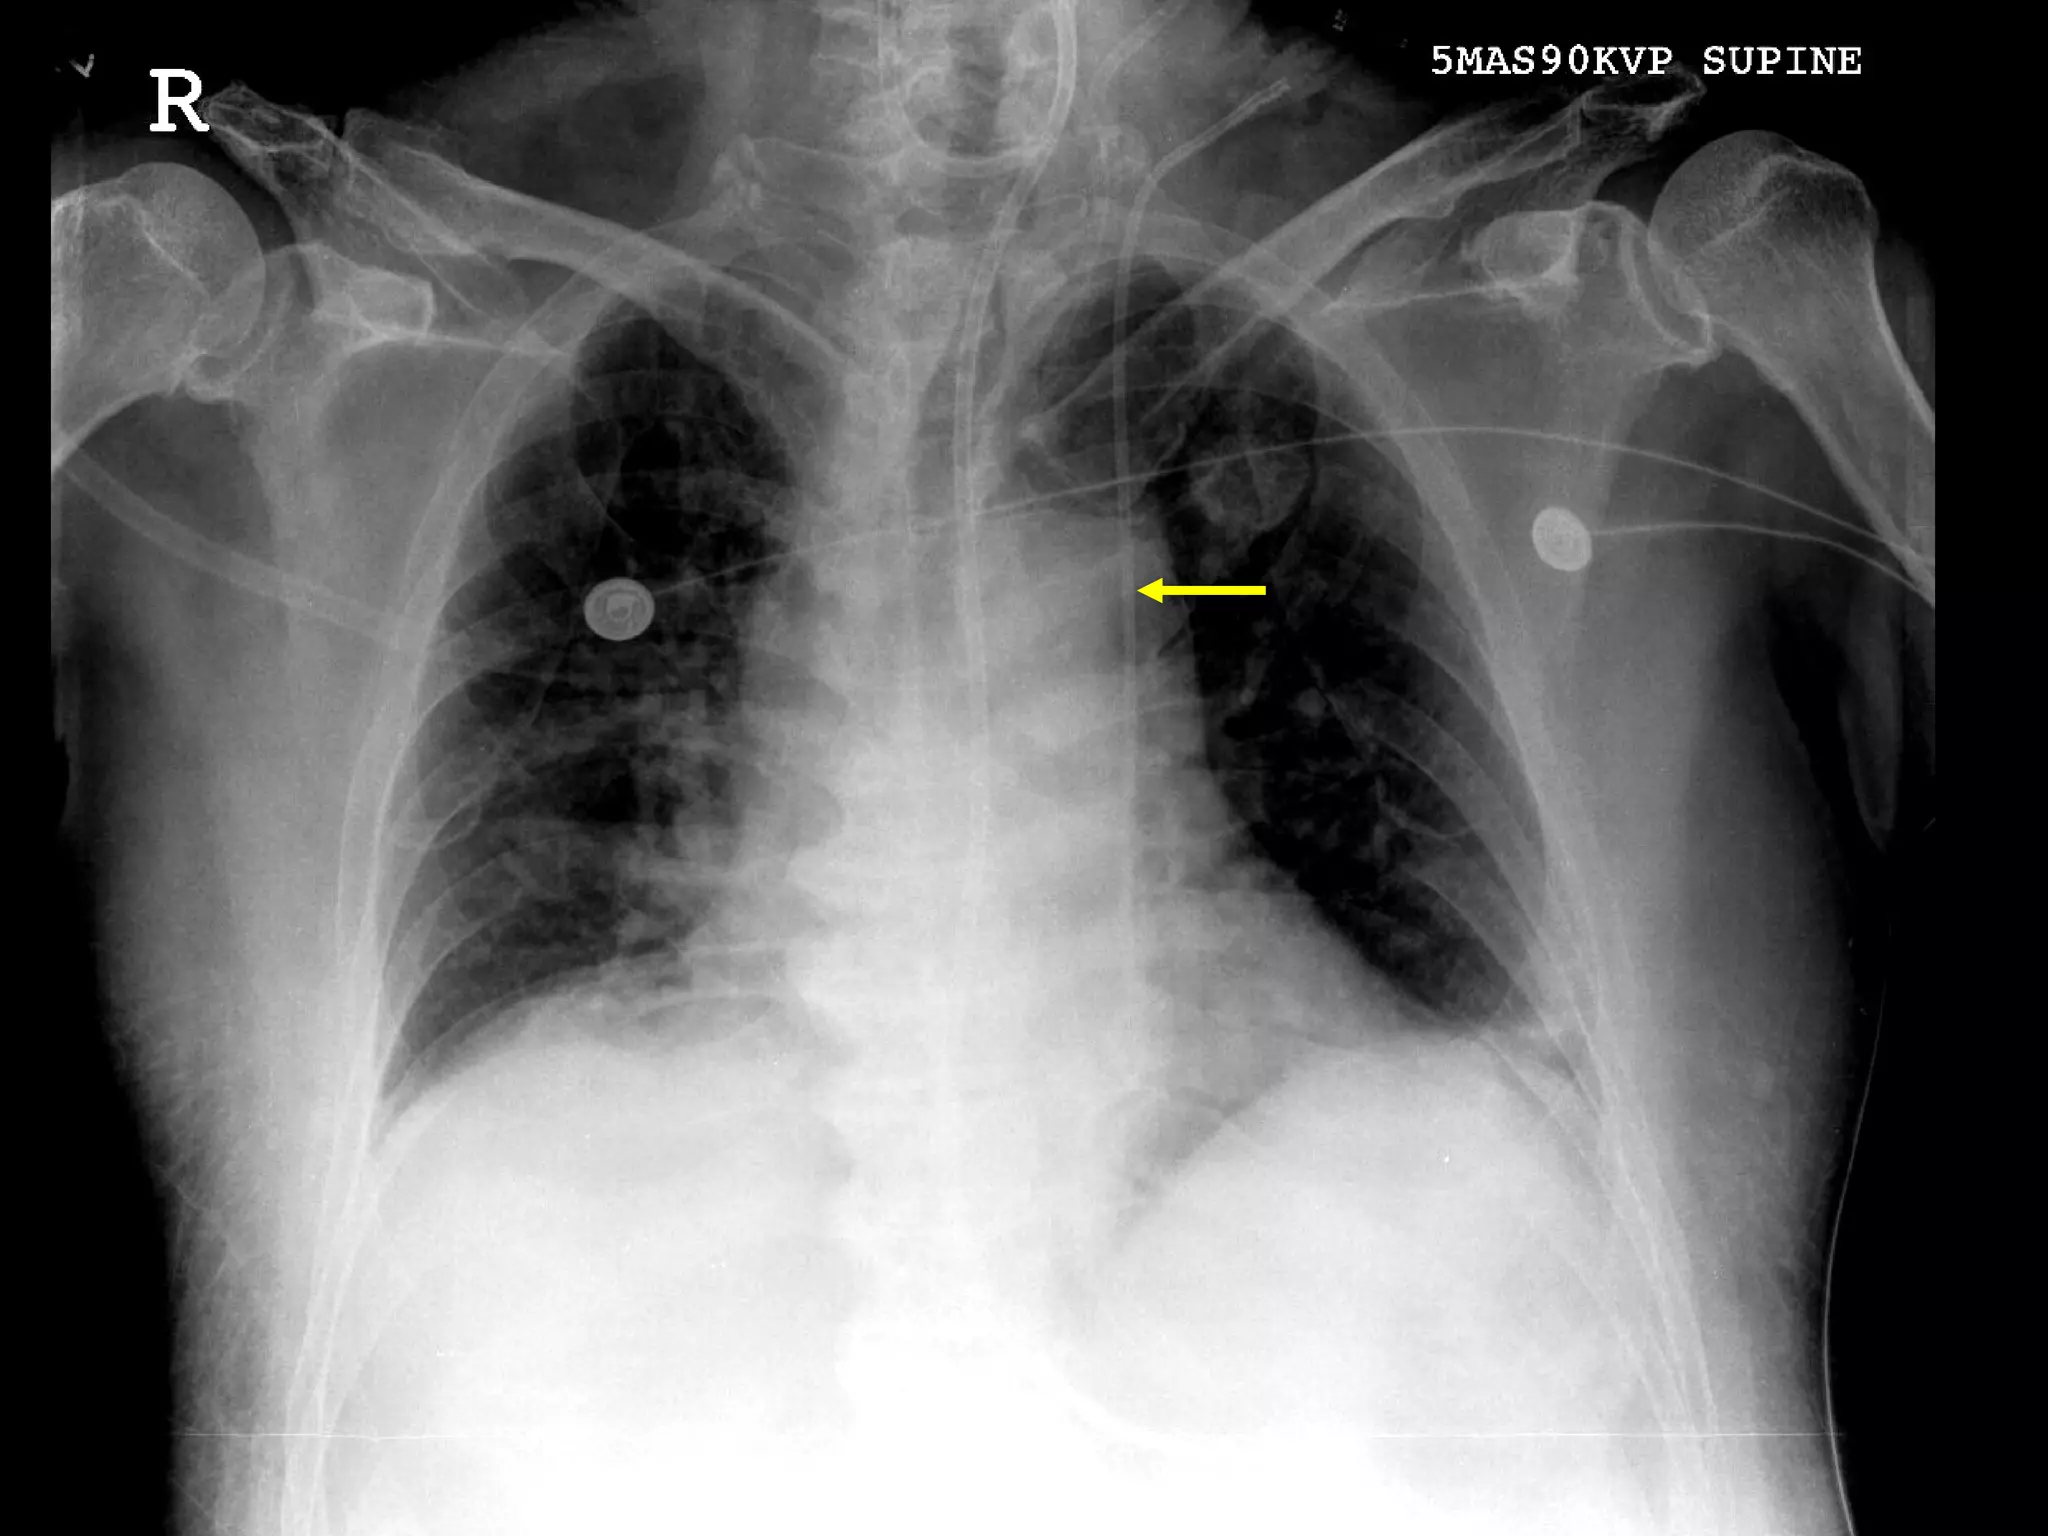

What’s Wrong With These Pictures?

ETT in too far

What’s Wrong WithThese Pictures?